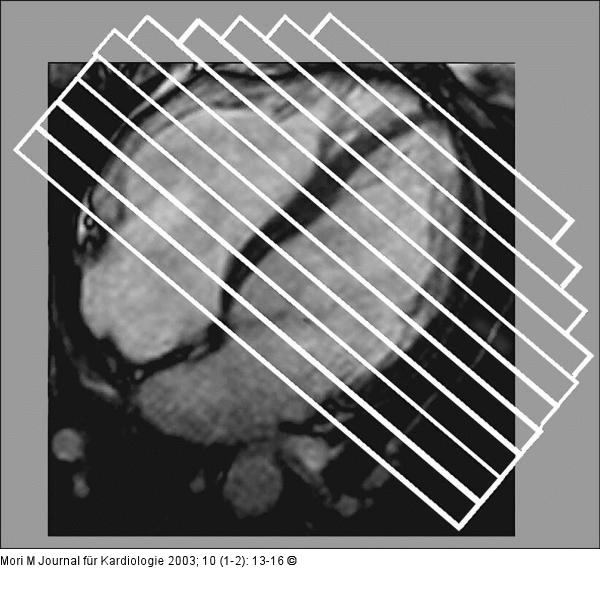

Abbildung 1: Kardiale Magnetresonanztomographie Planung der Kurzachsenschnitte: Lage der Schnitte zur Erstellung der Kurzachsen - Cineloops perpendikular zur horizontalen Achse (HLA). Abstand der Schichten: 10 mm |

Planung der Kurzachsenschnitte: Lage der Schnitte zur Erstellung der Kurzachsen - Cineloops perpendikular zur horizontalen Achse (HLA). Abstand der Schichten: 10 mm |